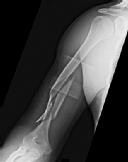

A 72-year-old female on prolonged bisphosphonate therapy presents with thigh pain.

Radiographs show a fracture of the femoral shaft. Which of the following radiographic features is most characteristic of an atypical femur fracture associated with bisphosphonate use?

Explanation

Atypical femur fractures (AFFs) associated with prolonged bisphosphonate therapy have specific major criteria defined by the ASBMR. These include a location anywhere from just distal to the lesser trochanter to just proximal to the supracondylar flare, transverse or short oblique orientation, non-comminuted (or minimally comminuted), and originating at the lateral cortex with localized periosteal or endosteal thickening ('beaking').